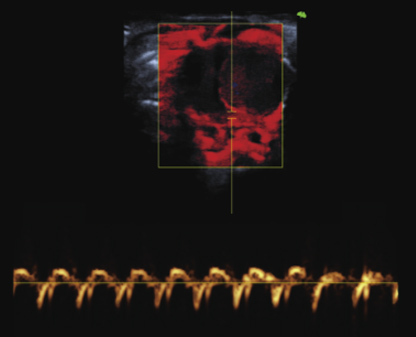

组织、器官、肿瘤鉴定血管密度、结构和流量,实现生物标记物可视化二维显示

造影剂定量分析,包括生物标记物显示心脏壁运动及strain